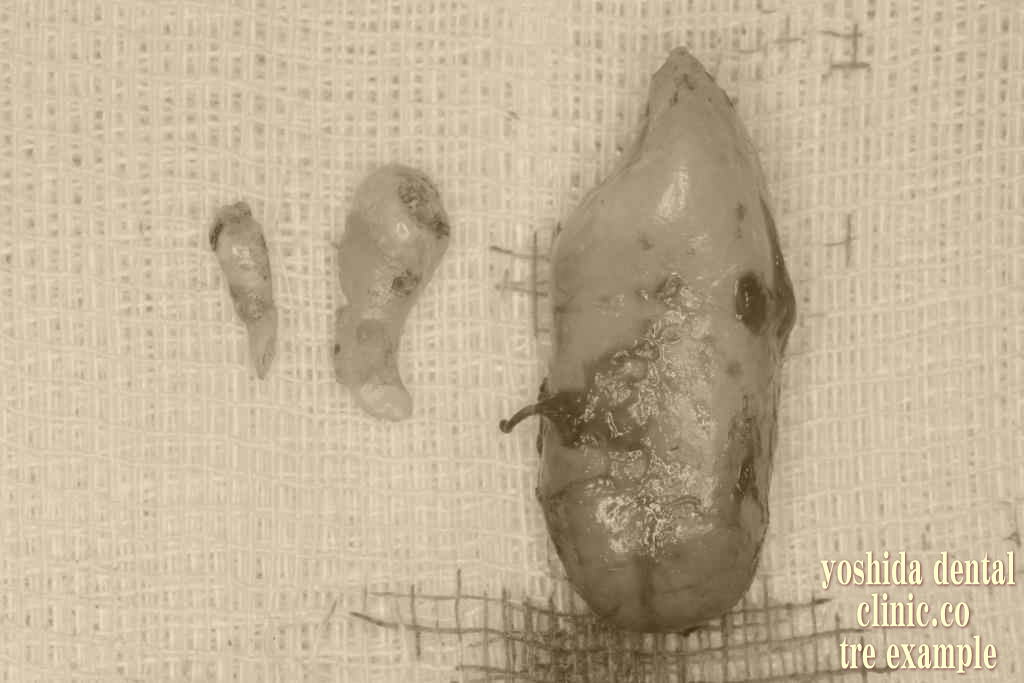

口腔内の歯牙腫瘍摘出術

歯牙腫瘍摘出前 歯牙腫瘍摘出後

右下の歯茎の中で歯が複数できる腫瘍確認 歯牙腫瘍を全て摘出しています。計5歯。

歯牙腫瘍摘出前 歯牙腫瘍摘出中歯牙腫瘍摘出後

左上の歯茎の中で歯が複数できる腫瘍確認 歯牙腫瘍を摘出後、計2歯。